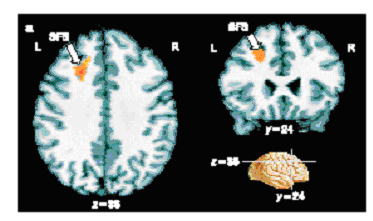

([http://www.nimh.nih.gov/press/prdecisionhub.cfm US government image]. {{PD}}) |

- (del) (cur) 04:49, 11 September 2005 . . en:User:JWSchmidt JWSchmidt ( en:User_talk:JWSchmidt Talk) . . 373x221 (80738 bytes) ( US government image. { { PD } })